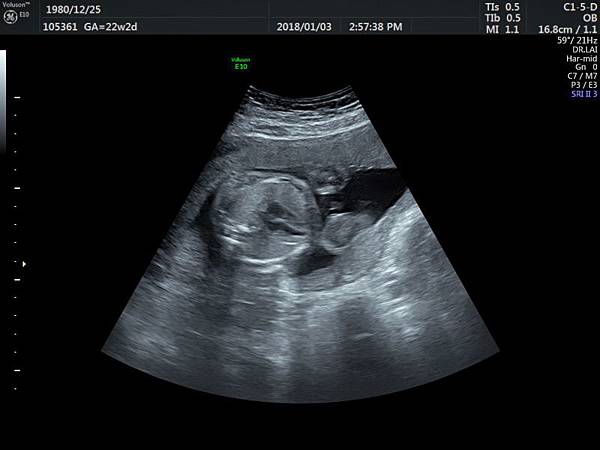

有一對夫妻因為我之前迷走性右側鎖骨下動脈(ARSA)的診斷而選擇孕兒診所,先生告知因為曾經有一個產前被我診斷ARSA的個案在他們醫院出生,他們花很久的時間才證實新生兒有ARSA,他覺得我很厲害,我有點不好意思,其實對專家而言,胎兒時期要診斷ARSA比新生兒容易,原因是胎兒時期超音波下,這條血管可以很清楚的被看到,它是從主動脈出來經過氣管的後面由左側繞到右側(附圖 1.),但是新生兒心臟超音波要看這條血管有困難,因為氣管擋住這條血管,醫師只能靠主動脈的第一個分支(brachiocephalic artery)沒有呈現 y 的特徵(附圖 2.),所謂 y 是brachiocephalic artery正常是會分出兩個分支(附圖 3.4.),一個是right common carotid artery,另一個是right subclavian artery,如果有迷走性右側鎖骨下動脈( ARSA ),就不會有正常的right subclavian artery,所以在新生兒的右頸部就不會看到 y的特徵,新生兒要直接看到迷走性右側鎖骨下動脈( ARSA)這條血管真的要花很多的時間(參考第51篇文章)。